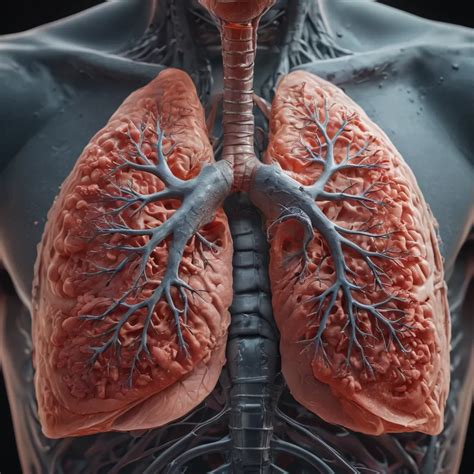

Emphysema is a chronic lung disease that affects millions of people worldwide. It is characterized by the destruction of the alveoli, the tiny air sacs in the lungs, leading to shortness of breath and other respiratory issues. One of the most pressing concerns for individuals diagnosed with emphysema is understanding their emphysema life expectancy. This post aims to provide a comprehensive overview of emphysema, its impact on life expectancy, and factors that can influence the progression of the disease.

Emphysema is a type of chronic obstructive pulmonary disease (COPD) that primarily affects the lungs. It is often caused by long-term exposure to irritating gases or particulate matter, most commonly from cigarette smoke. The disease leads to the breakdown of the alveoli, which are responsible for exchanging oxygen and carbon dioxide in the lungs. As a result, individuals with emphysema experience difficulty breathing, especially during physical exertion.